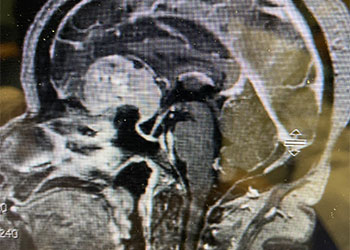

Brain:

Pituitary Tumor with Cushing’s Disease

Author: Michael Brisman M.D., F.A.C.S., Read More!